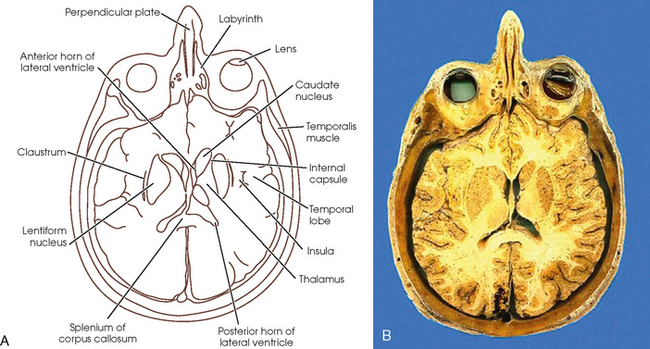

Sectional anatomy of the structures of the brain as viewed with ct mri and pet fusion imaging. It is superior to the upper pole of the right kidney whereas the left adrenal gland is anteromedial to the upper pole of the left kidney.

These labeling exercises are to aid the viewer in learning the sectional anatomy of the brain.

Learn cross sectional anatomy brain with free interactive flashcards. What is the term for the space that exists during fetal development and that disappears in most children during infancy. This video is from our cross sectional anatomy series.

Materials members learning exercises bookmark collections course eportfolios peer reviews virtual speakers bureau. Online mri ct sectional anatomy omcsa k anatomy is probably one of the most user friendly and convenient online interface for human anatomy atlas. Anatomical structures and specific areas are visible as interactive labeled images.

Mri of the brain. Anatomy of the encephalon mri in axial slices we created a brain atlas that is an interactive tool for studying the conventional anatomy of the normal brain based on a magnetic resonance imaging exam of the axial brain. Use the mouse scroll wheel to move the images up and down alternatively use the tiny arrows on both side of the image to move the images on both side of the image to move the images.